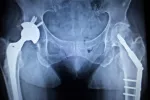

Diagnóstico de la osteonecrosis

Establecer el diagnóstico de la osteonecrosis puede entrañar una gran dificultad al inicio de la enfermedad, cuando no existe dolor ni otros signos en el paciente. Cuando estos sí están presentes, la sospecha diagnóstica puede motivar la realización de determinadas pruebas radiológicas que ayuden a confirmar o descartar el problema:

Se pueden establecer algunas fases en relación con los hallazgos de las pruebas radiológicas que determinan la evolución que está siguiendo la necrosis. Oscila desde una fase silente o asintomática, pasando por hallazgos de pérdida de osificación, formación de quistes en el hueso, hasta degeneración y colapso de la articulación afectada.